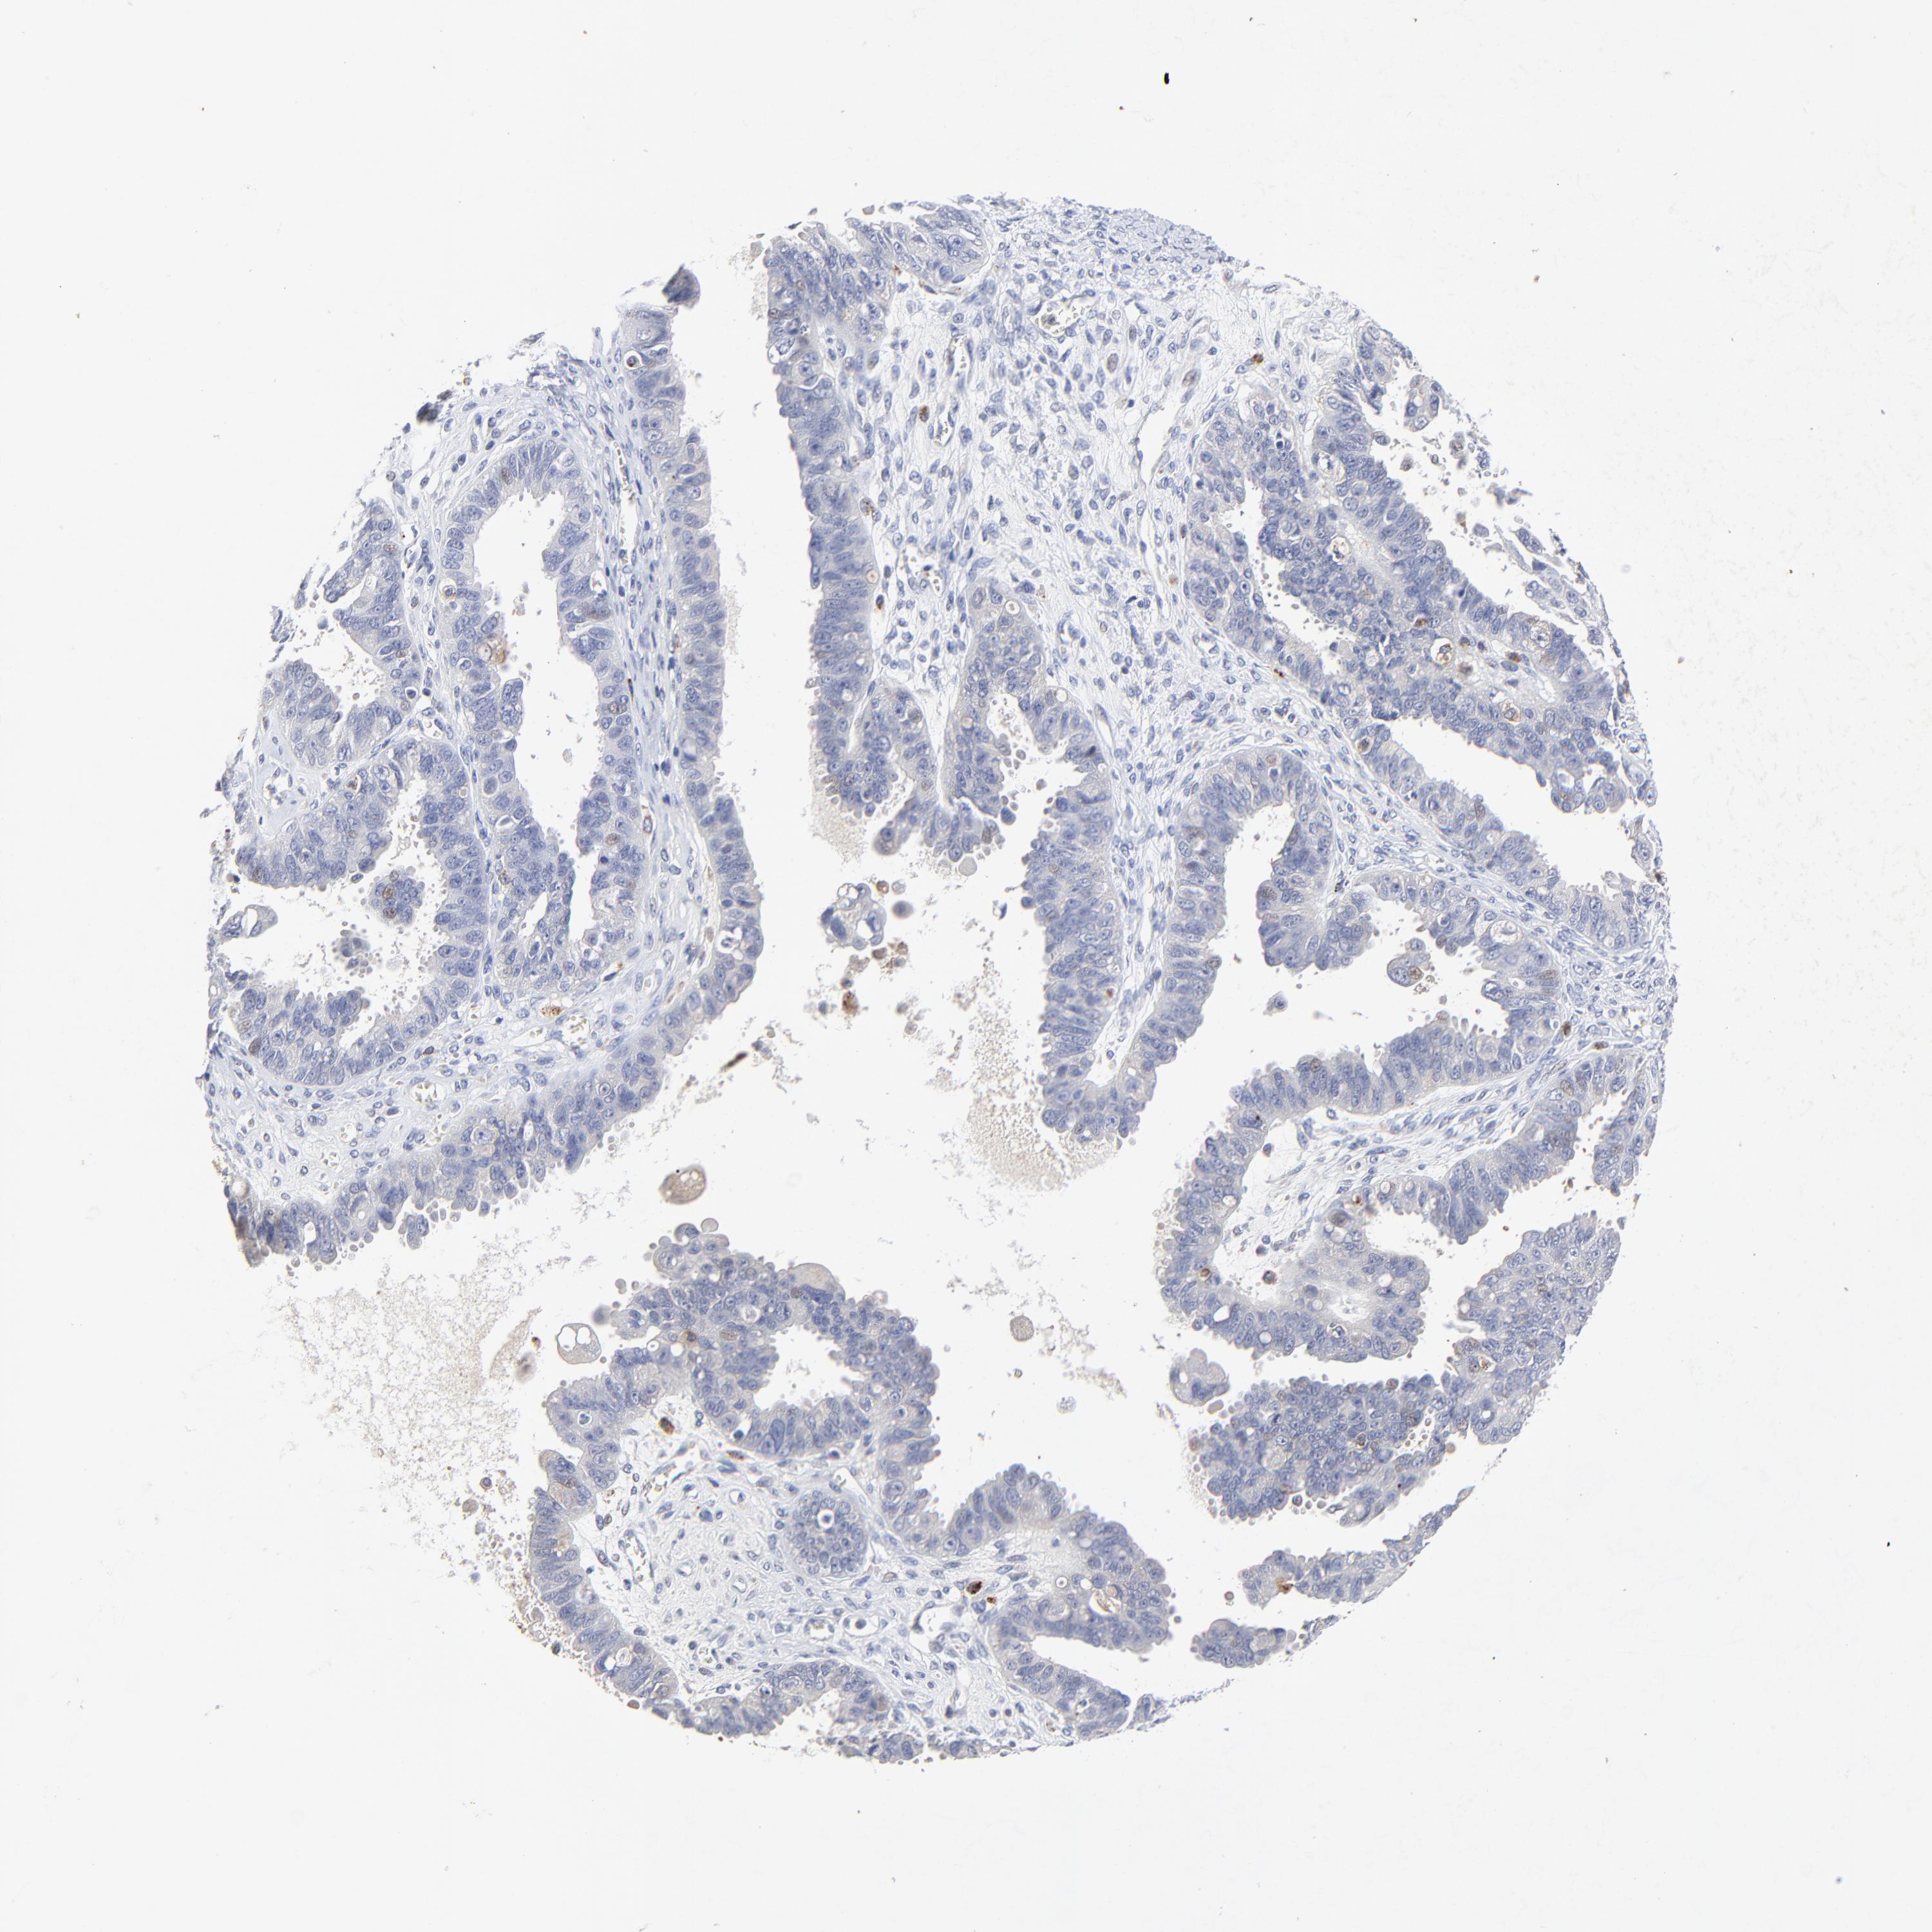

OVARIAN CANCER - Protein expressioni

A mouse-over function shows sample information and annotation data. Click on an image to view it in a full screen mode. Samples can be filtered based on level of antibody staining by selecting one or several of the following categories: high, medium, low and not detected. The assay and annotation is described here.

Note that samples used for immunohistochemistry by the Human Protein Atlas do not correspond to samples in the TCGA dataset.

Antibody stainingi

Antibody staining in the annotated cell types in the current human tissue is reported as not detected, low, medium, or high, based on conventional immunohistochemistry profiling in selected tissues. This score is based on the combination of the staining intensity and fraction of stained cells.

Each image is clickable and will lead to virtual microscopy that enables deeper exploration of all samples and also displays staining intensity scores, fraction scores and subcellular localization as well as patient and tissue information for each sample.

Antibody HPA003162

Cystadenocarcinoma, mucinous, NOS

Carcinoma, endometroid

Cystadenocarcinoma, serous, NOS

Carcinoma, NOS